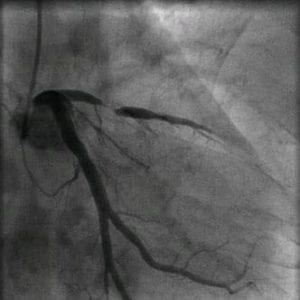

Authors: Back Kim MD, Nay Htyte MD & Tae An Choi, ANP Heart Vein NYC, New York, New York 67-year old male with exertional mid-sternal read more